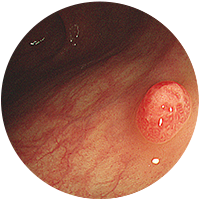

선종

-

2

진행성대장암